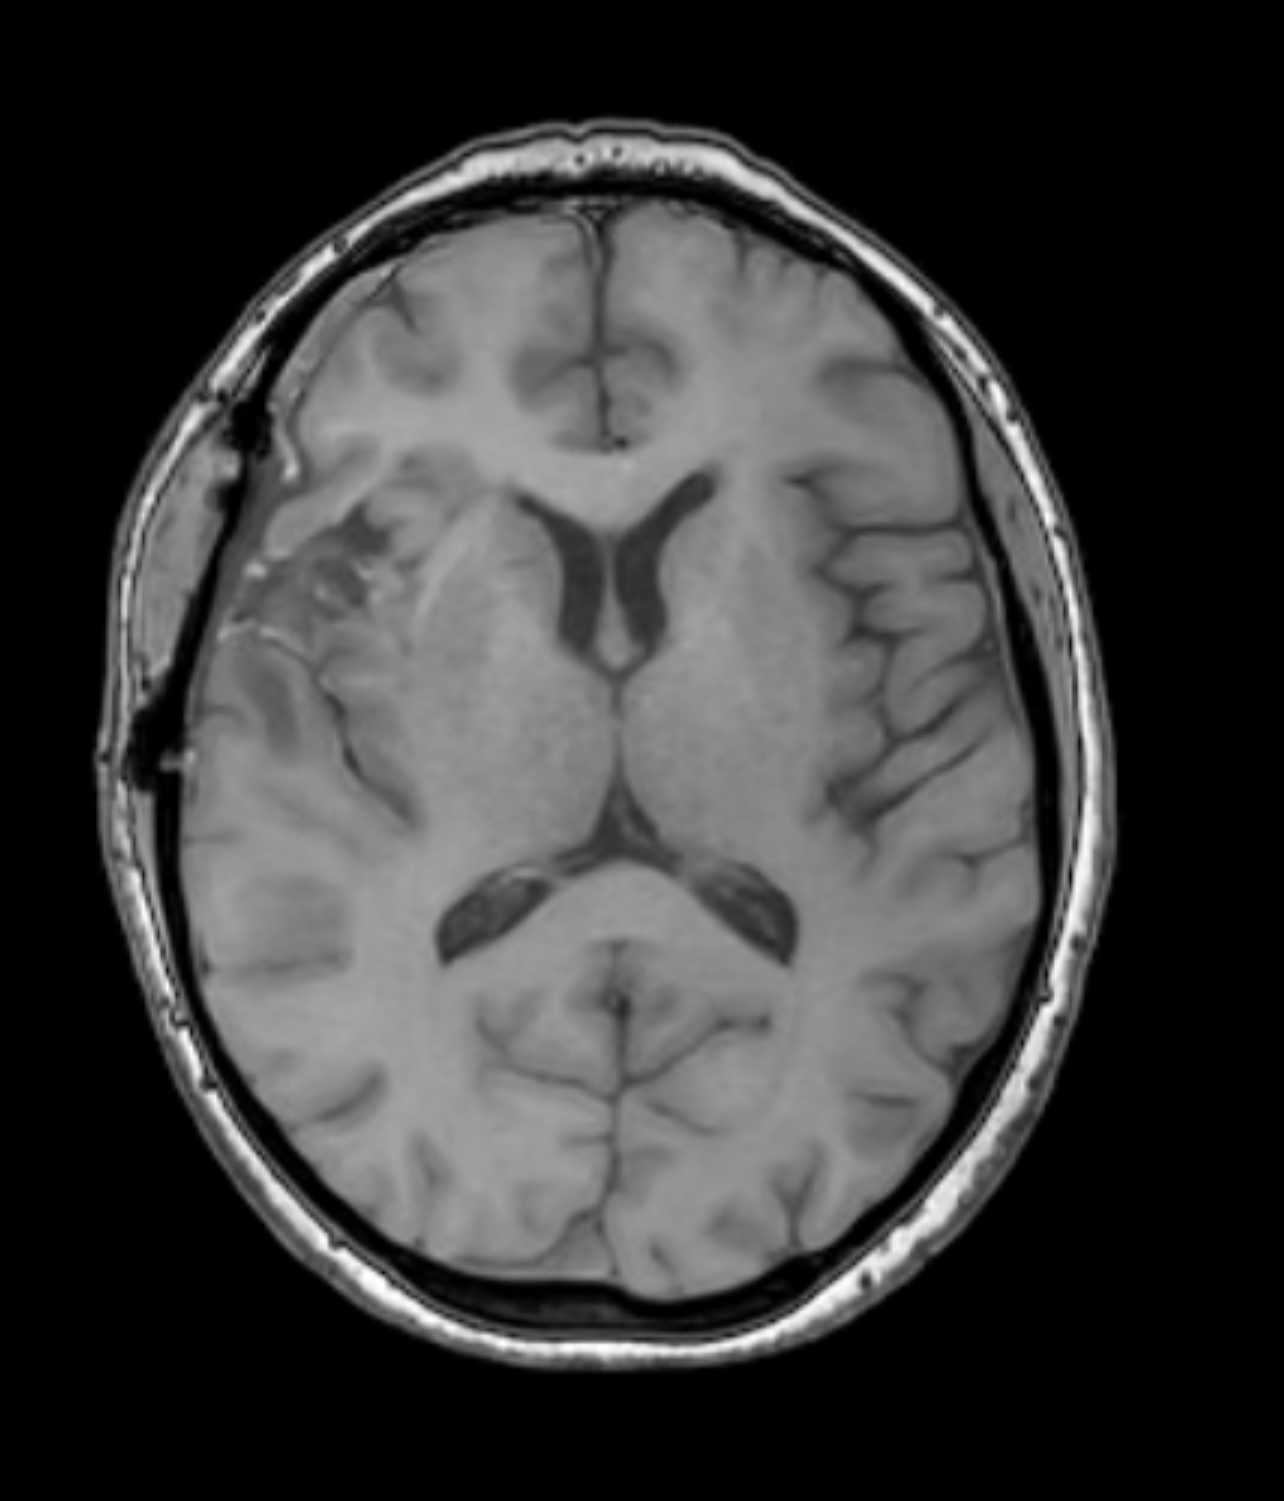

In the image above, the December MRI (pre-treatment) is on the right side, while the March MRI is on the left side. These two images show that no new cancer is growing, and also that the brain is in process of healing itself: filling in the gap where the tumor was removed.

They said that the cavity will always be there – that she’ll always have it to some degree. But even so, there is such a clear difference in the image on the right and the one on the left.

What you can see here are the side-by-side comparisons of the same kind of scan in the same “slice” (cross-section area of the brain). The scans show NO GROWTH of cancer, and even a small reduction in the amount highlighted by the contrast.